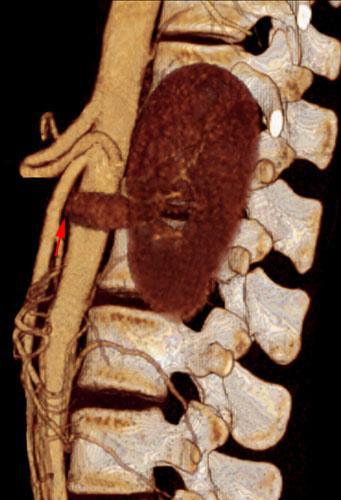

Síndrome del cascanueces retroaórtico